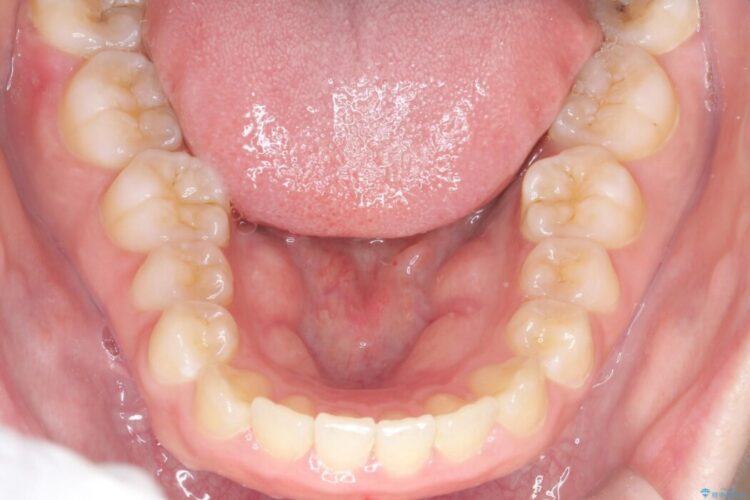

矯正検査の結果、前歯が外側に強く倒れ込んでいる「唇側傾斜(しんそくけいしゃ)」が認められ、口元の突出感の原因になっていました。

この傾斜を根本から正し、前歯を十分に後方へ下げるスペースを確保するため、上下左右の4番を抜歯し、目立ちにくい審美ワイヤー装置にて治療を行うこととしました。